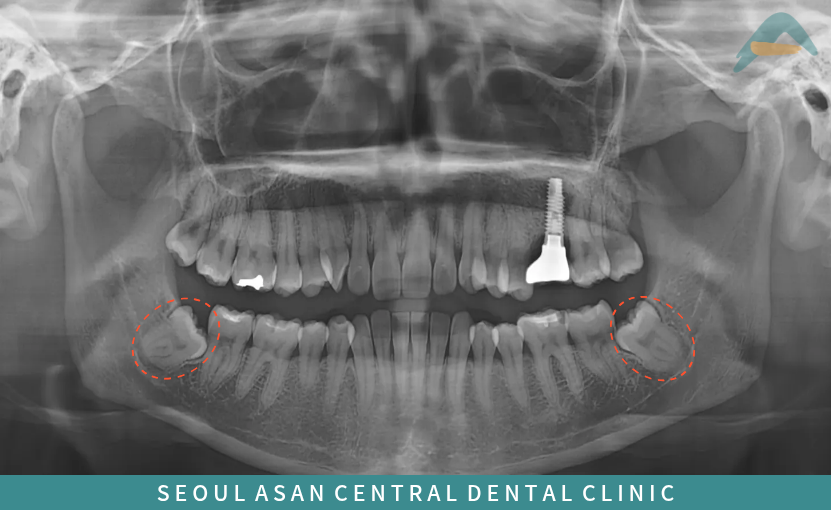

사랑니는 올라오는 시기나 형태가

사람마다 다 다를 수 있으며

턱뼈의 공간 부족으로 인해

비정상적인 방향으로

맹출 하는 경우가 많아

다양한 문제를 유발할 수 있어

사랑니 발치를 진행하기도 합니다.

다른 치아들과 같이

똑바로 올라온다면 다행이지만

옆으로 누워있거나

잇몸 뼈 속에 매복되어 있는 경우에는

뽑아주는 것이 좋으며,

이렇게 사랑니가 매복되어 있는 상태라면

주변 치아와 신경, 턱뼈 구조물에

영향을 줄 수 있기에

발치 난도가 더 높아지고

더욱 까다로운 요구가 필요한데요.